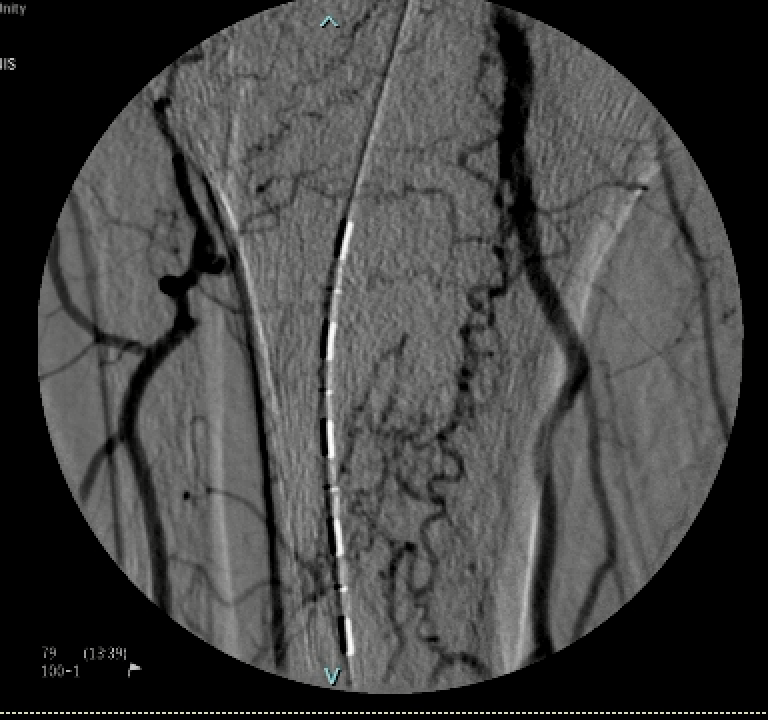

.@LucasRCmd, MPH; @HiroSparks, MD; Kara E. Masterson, MSN, NP; Scott J. Genshaft, MD; @AdamPlotnik, MD; and Siddharth A. Padia, MD, contributed to this open access article. See what they've been working on! brnw.ch/21wPx6v